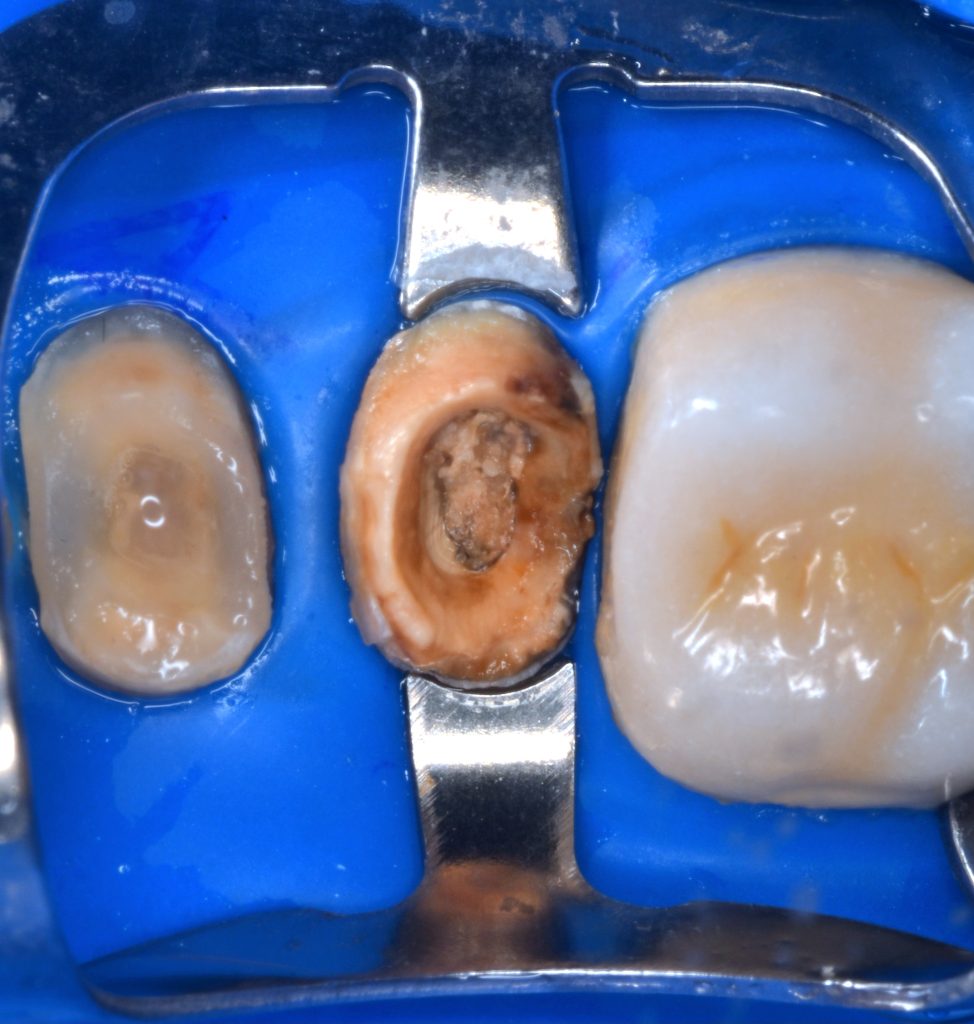

Deep margin elevation using circumferencial Copper bands

Elevation by snow plow technique n

And final design to receive to monolithic lithium disilicate restorations